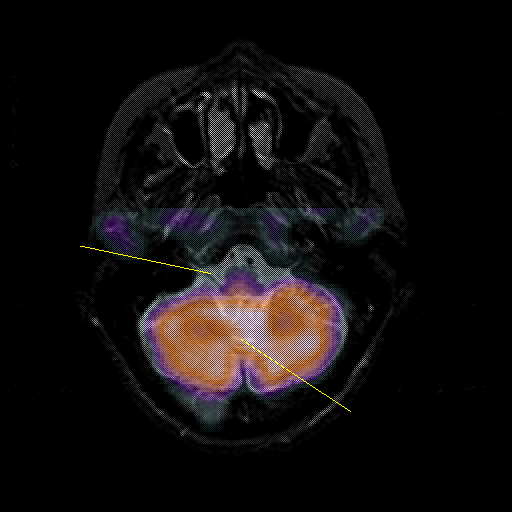

overlay : Slice 11

Slice 11